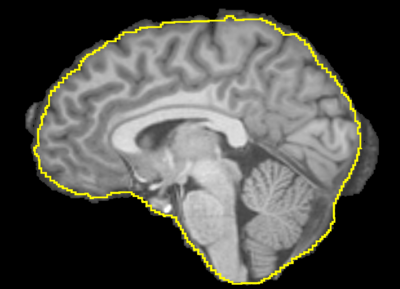

Image:T1_BET.png|A T1 weighted MRI image with the brain extracted using BET.

This is a CLI module for Brain Volume Refinement (BVeR) tool, which is useful to correct brain segmentation errors that may appear in commonly brain extraction methods. The BVeR algorithm was extensively tested on structural MRI images (T1 and T2) of normal individuals. Further details are found at PAPER

• It is frequent to appear segmentation errors (outliers) in commonly used brain extraction algorithms (BET, FreeSufer, BSE, AFNI, ROBEX, etc), thus the BVeR application can be helpful.